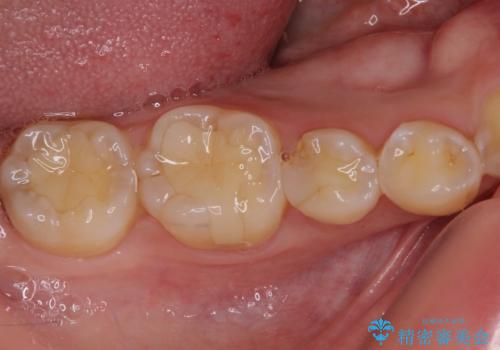

ディープバイトが改善されたことで、顎への負担が軽減され、更には上顎前歯の突出感も改善することができました。

矯正治療後には欠けてしまった修復物をセラミックインレーにて修復治療しました。